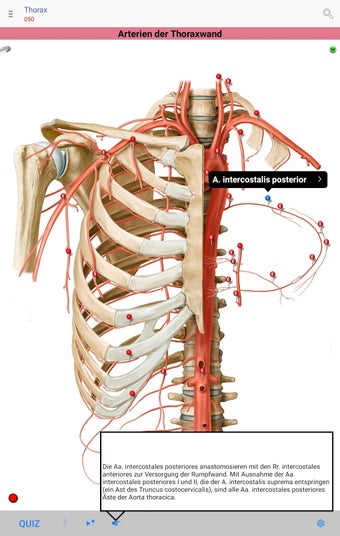

The app consists of different sections, each of which contains information about a specific part of the body. You will learn about the different organs, as well as the muscles, bones, and other important structures. You can test yourself with a unique quiz that consists of multiple-choice questions.